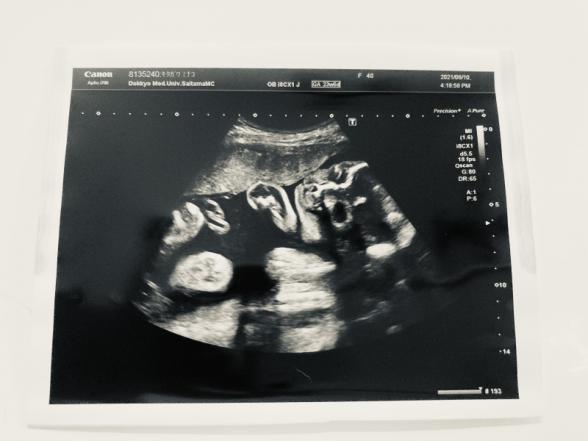

先日のエコーでよく見ると、口唇口蓋裂では?と不安に思えて仕方ありません。角度とかそういうのもあるのかもしれませんが、次回2週間後の検診まで気が気でなくて…どう判断されますか?

赤ちゃんのエコーで、口唇口蓋裂なのではないかとご心配をされているのですね。

エコーでわかることもありますし、はっきりとわからず、生まれてから最終的な診断が出ることになりますよ。